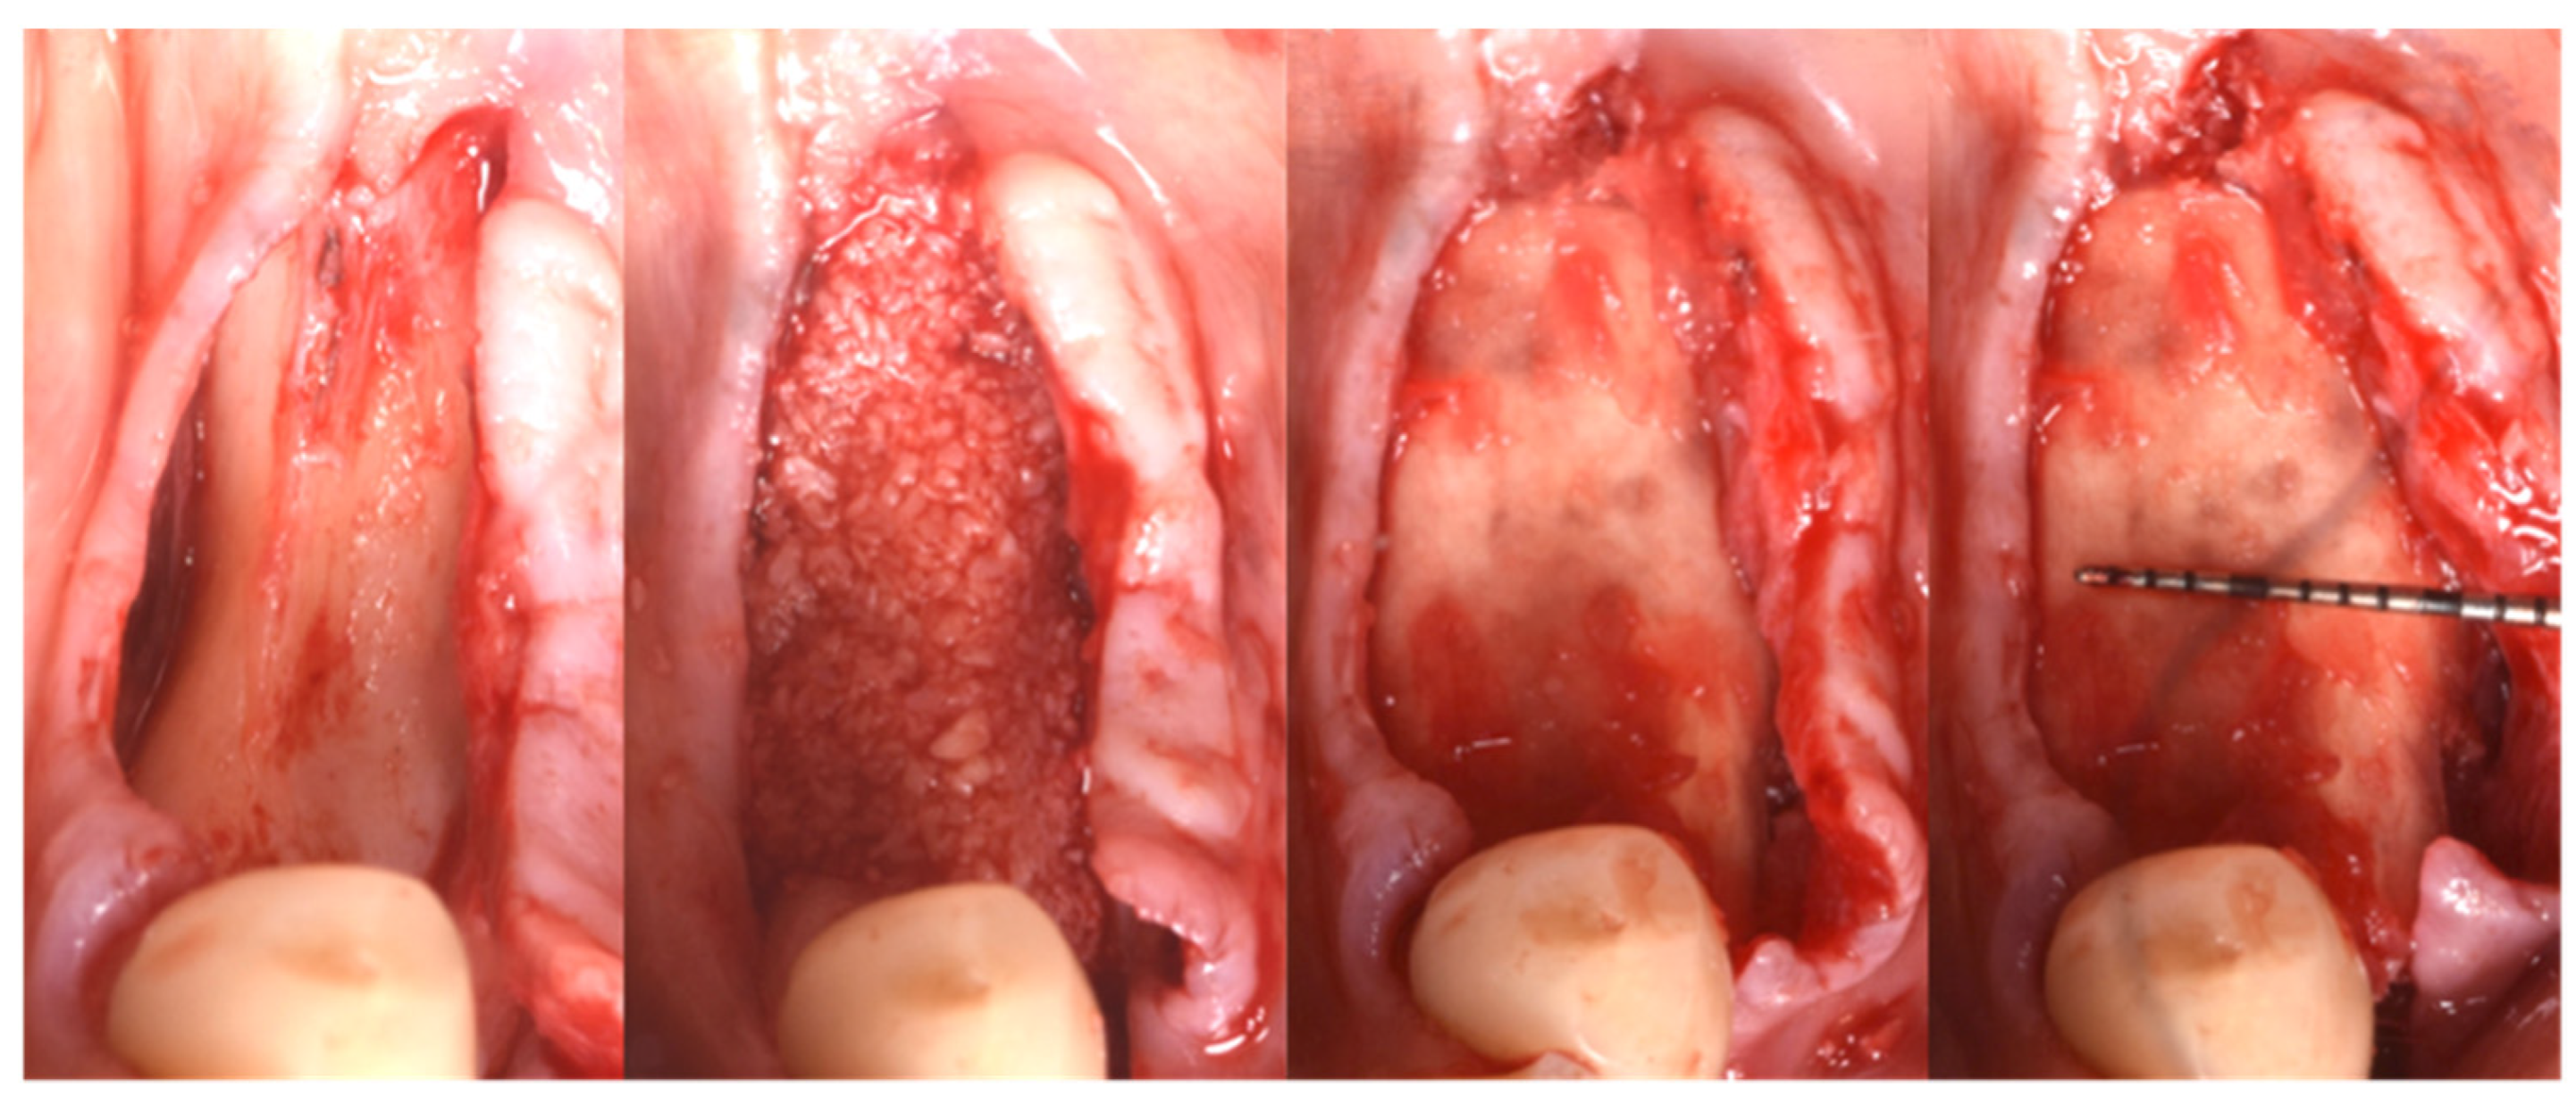

3.4. Implant Insertion

In this case of important bone augmentation, a healing period of 8 months was observed. Indeed, biomaterials, such as FCS, require a longer time than autogenous bone. No complications were experienced during the follow-up. At the end of the healing period, CBCT was performed to plan the implants’ insertion (Figure 8). It was pleasant to observe that the GBR provided the desired volume augmentation for the ridge. The CBCT showed a horizontal and vertical ridge augmentation of 8 mm and 8 mm, respectively.

Figure 8.

New volume observed 8 months after surgery.

Two implants (Institute Straumann, Basel, Switzerland) of 4 × 12 mm and 5 × 8 mm were inserted in the 3.4 and 3.6 areas, respectively (Figure 9a). The final prosthesis was manufactured with a digital workflow and delivered after three months. The patient was monitored with clinical and radiographic evaluations 12 and 18 months after prosthetic loading. The clinical examination and the digital scans at 12 months of follow-up proved the efficacy of the regenerative approach (Figure 10 and Figure 11). The comparison between 12 (Figure 9b) and 18 month (Figure 9c) radiographs showed stability of the bone crest around the dental implants. Furthermore, a progressive mineralization of the regenerated area was also evident (Figure 9a–c).

Figure 9.

Periapical radiographs (a) immediately after implant placement (Institute Straumann, Basel, Switzerland), (b) after 12 months, and (c) after 18 months of prosthetic loading.

Figure 10.

Clinical evaluation after 18 months of prosthetic loading.

Figure 11.

Scan taken after 18 months of prosthetic loading.